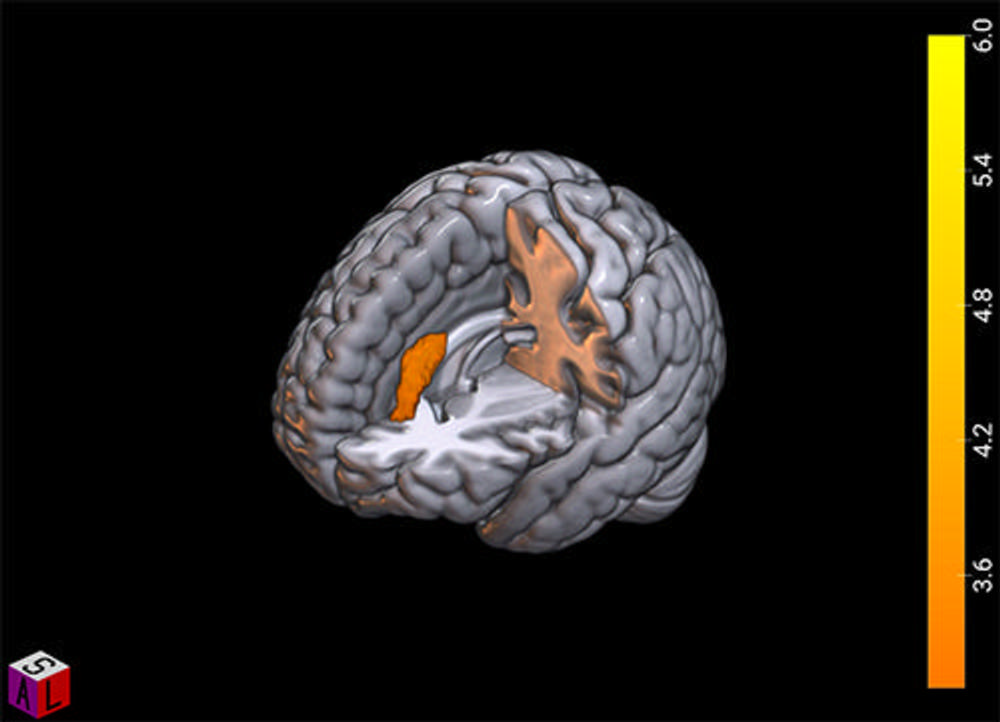

Figure 4. The contrast of winning and losing in the “good fanatic brain.” The image shows in warm colors the activity related to a significant victory. The blue scale represents the activation related to a significant loss; this pattern is congruent with the Mentalization Network, which suggests a rationalization process of the pain evoked by the losing scenario.

High-res (TIF) version